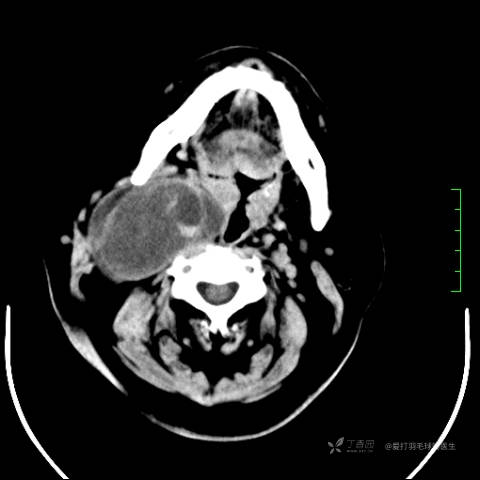

中年女性,全身多处“疙瘩”,长了切,切了又长,分型是关键,已公布结果。

患者性别:女

患者年龄:44岁

主诉:患者因反复右侧腰痛伴右下肢麻木2年余入院。

简要病史:自诉右甲状腺功能亢进症多年,规律服药,平素多有心悸、胸闷、活动后明显。既往腰椎椎管内肿瘤切除术。